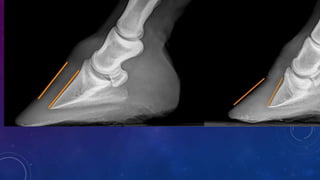

• Su veterinario puede proporcionarle información

de la condición en la que se encuentra su caballo

basándose en el uso de radiografías y/o la

respuesta al tratamiento. Las radiografías

muestran el grado de rotación del tejuelo(rotación

de l tercera falange en imagen). Esto le ayudará a

tomar una decisión que sea la mejor para su

caballo y ayudará al herrador con el herraje

terapeútico.